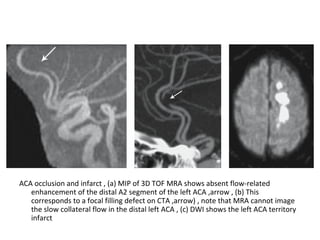

ACA occlusion and infarct , (a) MIP of 3D TOF MRA shows absent flow-related

enhancement of the distal A2 segment of the left ACA ,arrow , (b) This

corresponds to a focal filling defect on CTA ,arrow) , note that MRA cannot image

the slow collateral flow in the distal left ACA , (c) DWI shows the left ACA territory

infarct